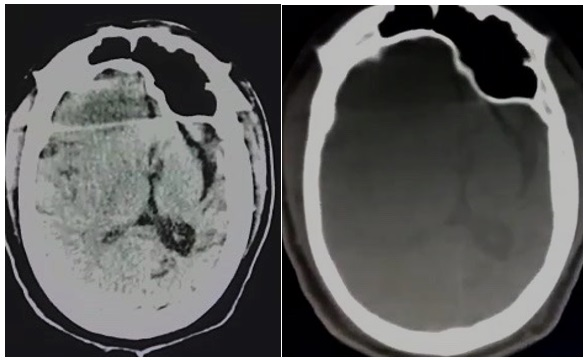

She underwent various cross-sectional imaging. Axial Non-contrast Computed tomography (NCCT) of brain depicts left cerebral hemisphere atrophy with dilatation of ipsilateral lateral ventricle with a bone window showing thickening of the left hemicranium, almost twice the thickness of that on the right side in the temporal region and hyperpneumatization of the left frontal sinuses [Figure 1].

The plain skull radiograph illustrates thickening of the calvarium and dilatation of the ipsilateral frontal and ethmoid sinuses. CT and MRI show unilateral atrophy of the cerebral hemisphere with an ipsilateral shift of the ventricle, widening of sulcal spaces on the involved side. It is associated with compensatory calvarium thickening, hyperpneumatization of the paranasal sinuses and mastoid cells and elevation of the petrous ridge [9]. In congenital hemiatrophy, when the insult occurs in utero, there is a shift of midline structures towards the disease side, but there is absence of sulcal prominence replacing the gliotic tissue. This is the salient feature differentiating congenital from acquired form [6].